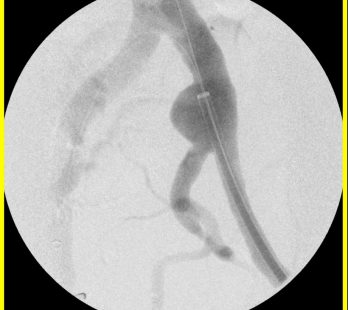

Hier sehen Sie die endovaskuläre Behandlung eines Aneurysma der A. iliaca communis links unter Erhalt der A. iliaca Interna links.